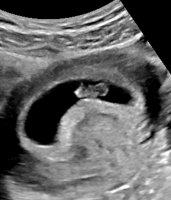

Fikk se en sprell levende liten sak på 4 cm på ultralyd idag, målt til 10+6 akkurat som mine beregninger etter eggløsning

En levende, perfekt liten figur her også i dagSom til og med ville vise frem tærne sine!

Så herligAlt så bra ut her i dag også! Ble satt fram noen dager igjen, så er et sted mellom 10+6 og 11+3. Var masse liv og bevegelsefikk med bilder og video hjem så samboer også får se.

Oj, såå kult med 3D bilde av lille

jeg er også mellom 10+6 (min beregning) og 11+2/3 (målt på UL). Men vår lille nekta fullstendig å samarbeide - opp og ned og fram og tilbake før man rakk å puste

jeg er også mellom 10+6 (min beregning) og 11+2/3 (målt på UL). Men vår lille nekta fullstendig å samarbeide - opp og ned og fram og tilbake før man rakk å puste så vi fikk ikke noen særlig gode bilder av skjermen. Jeg filma en bitteliten snutt i begynnelsen bare

Ja, veldig morsomt å se! Nå begynner det jo å ligne et lite menneskeSå herligNydelig liten da og så fint 3D-bilde